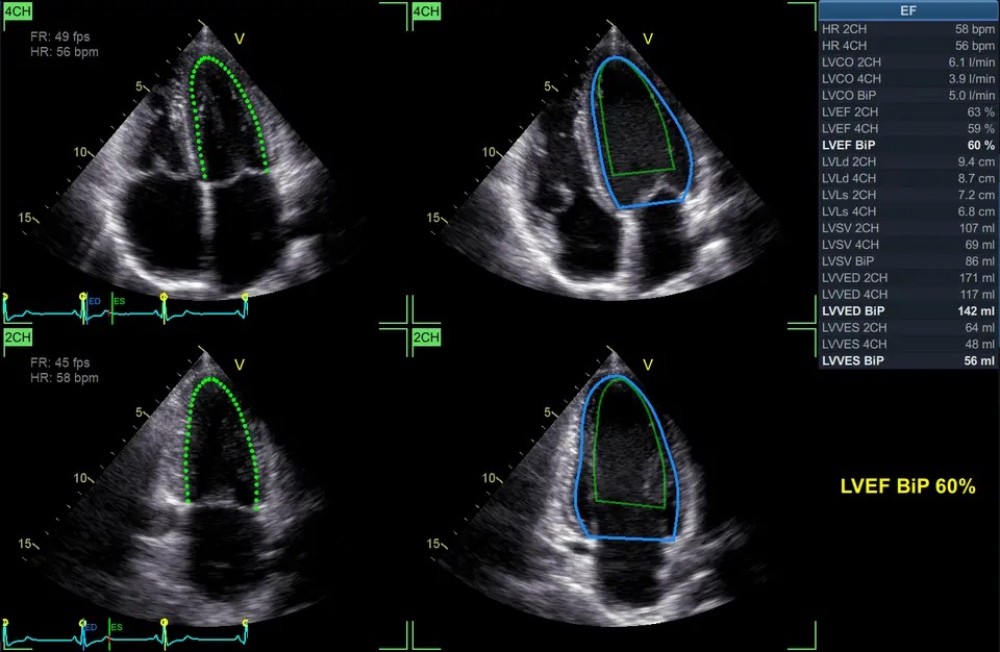

Açıqlama

Yeni proqram təminatı, məlumatları ekranda göstərilmədən əvvəl emal edir, artefaktları süzgəcdən keçirir və görüntünü daha aydın edir. GE Vivid E90 sistemi, əlavə nəzarət üçün 12 düymlük toxunma ekranı ilə birlikdə 22 düymlük yüksək çözünürlüklü OLED monitor ilə təmin olunur